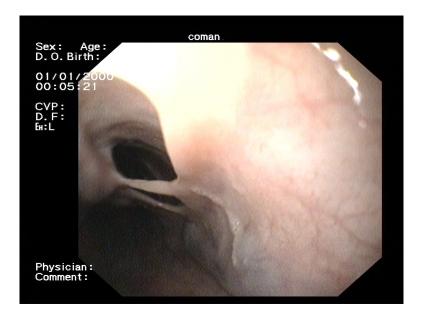

Spontaneous esophageal mucosal dissection in a patient with upper digestive bleeding and esophageal varices.

We present a case of mucosal esophageal dissection in a 44-year-old patient with alcoholic cirrhosis admitted for upper digestive bleeding. The endoscopic aspect was of chronic mucosal dissection in the esophagus and 3rd degree esophageal varices with red signs. To our knowledge, it is the only case with spontaneous esophageal mucosal dissection and portal hypertension with esophageal varices.